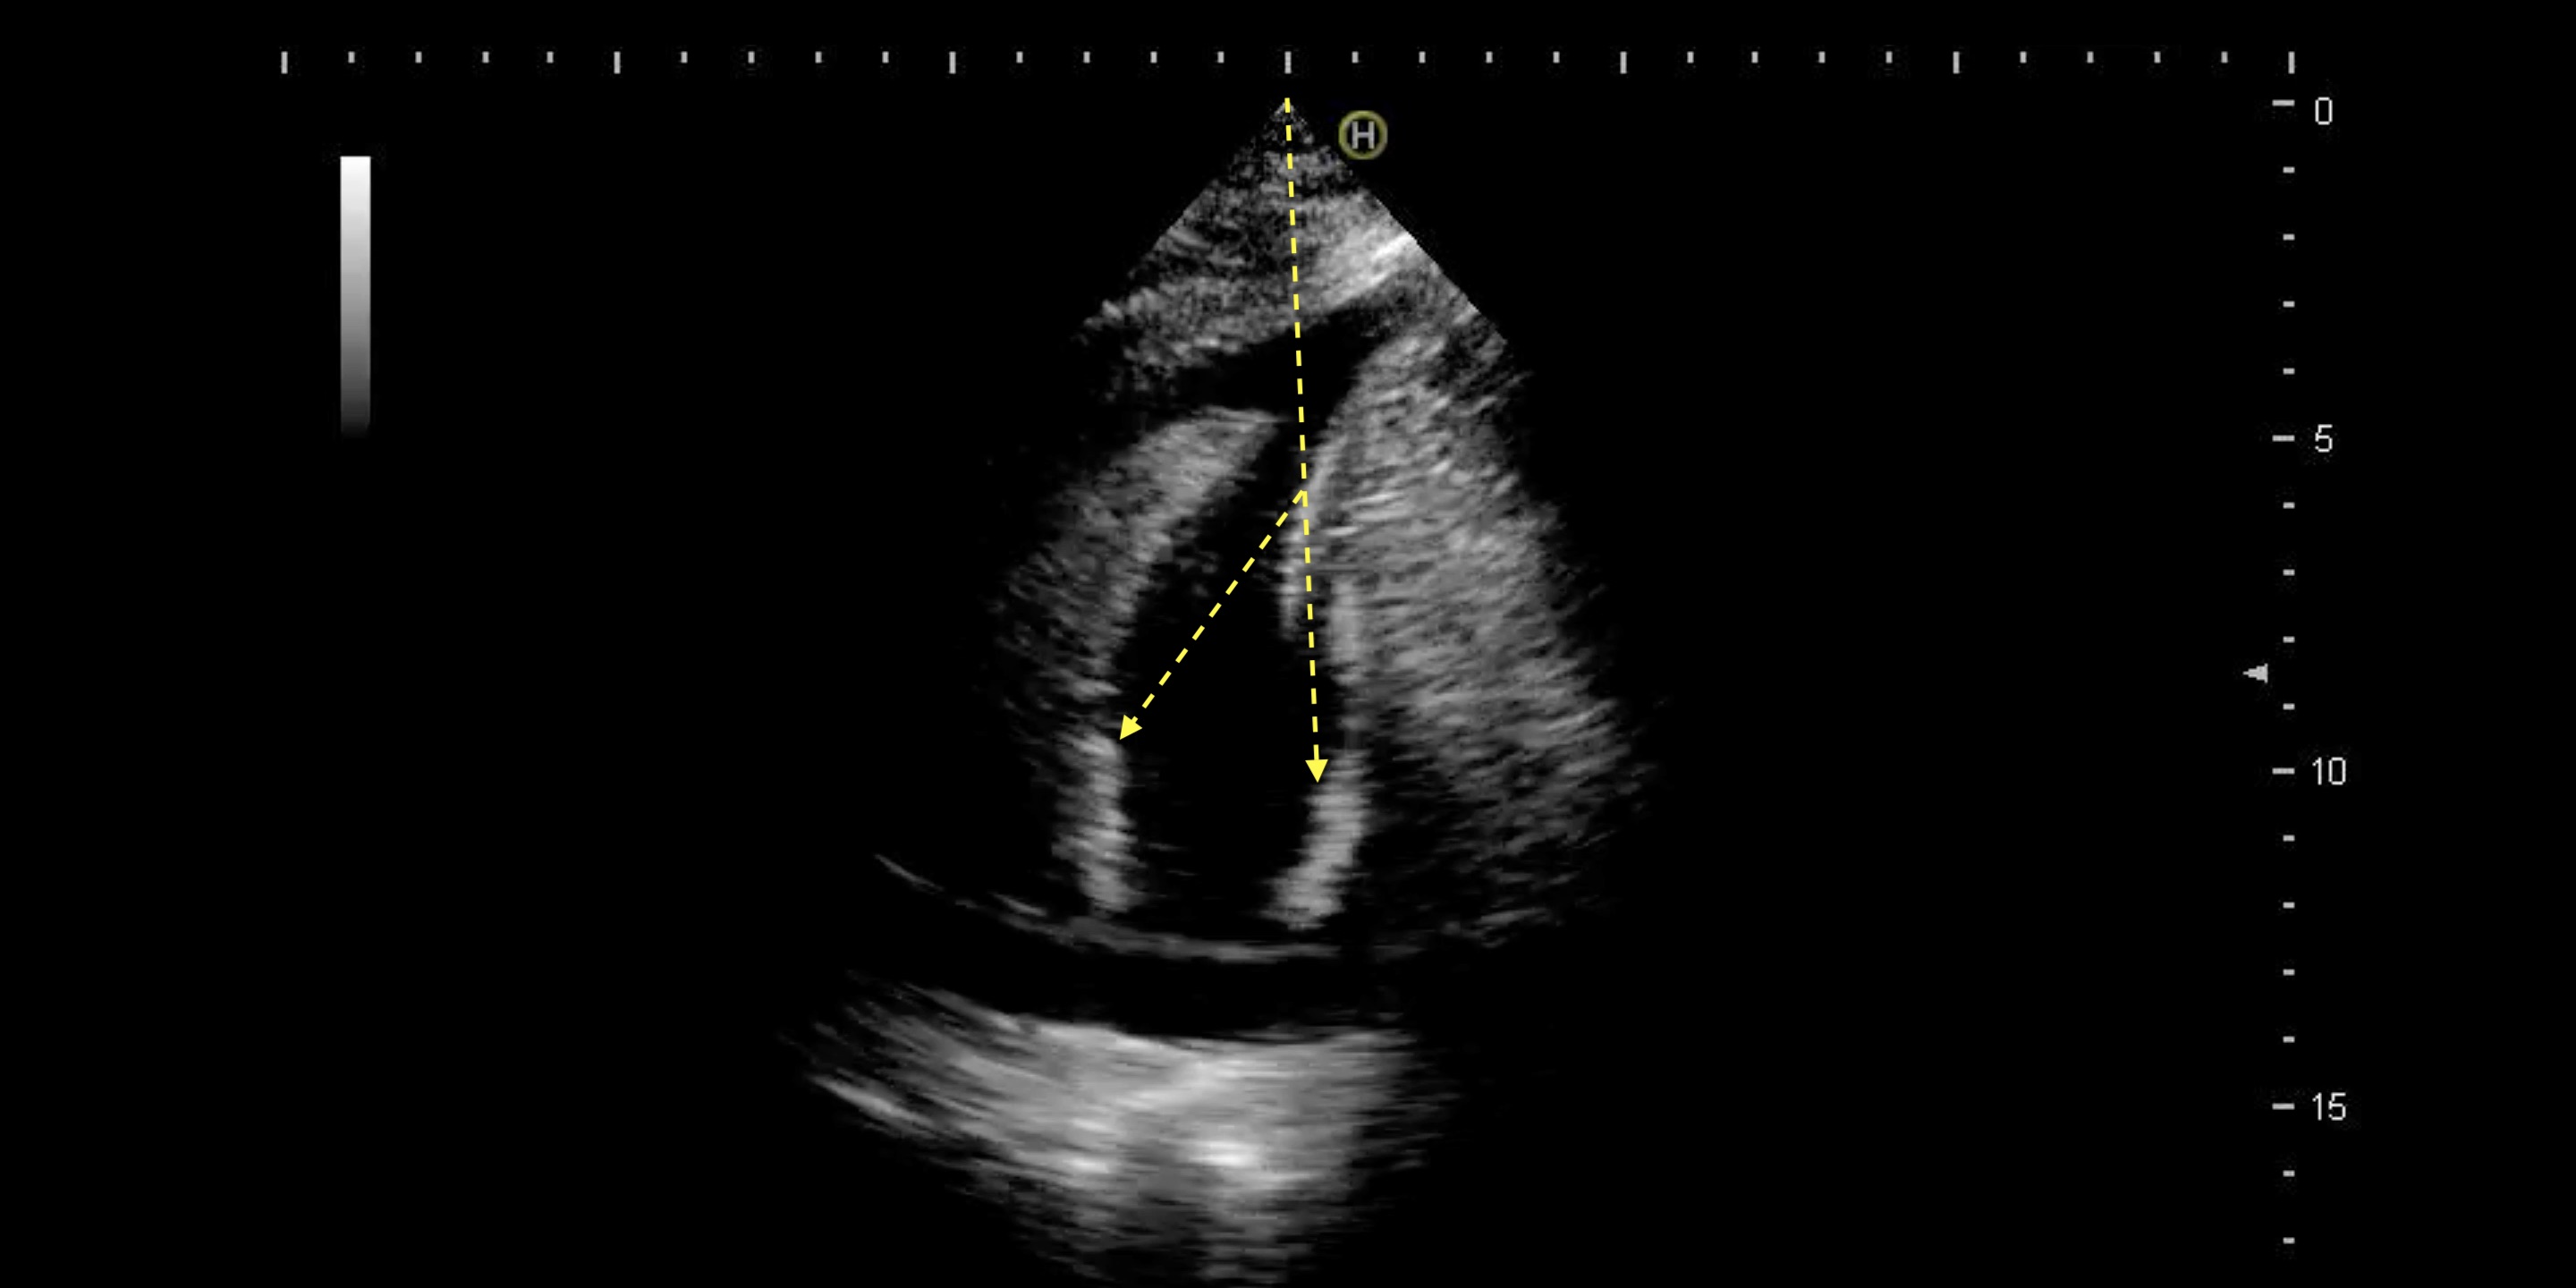

救急外来。胸痛。壁運動の低下部位はどこか?